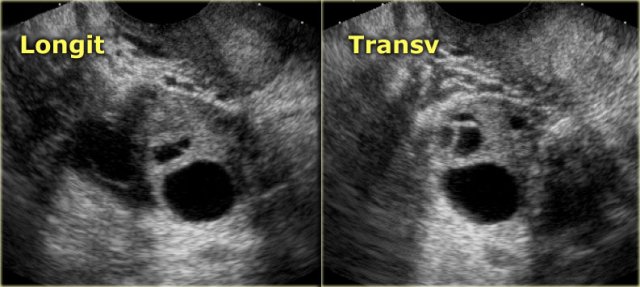

The ultrasound images show the right and left ovary: on both sides there is what appears to be a solid lesion.

There is however good through transmission, which indicates that we are probably dealing with hemorrhagic cysts.

On Doppler US (not shown) there was no vascularity.

Continue with the MR examination.